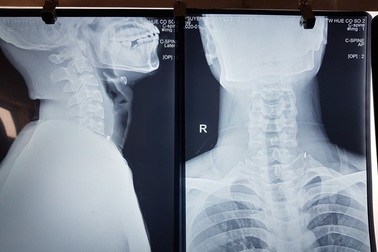

Phẫu thuật lấy mảnh sắt găm vào cổ thợ sửa ô tôNgày 20/1, Bệnh viện Trung ương Huế Cơ sở 2 cho biết đã thực hiện thành công ca phẫu thuật lấy dị vật găm vào vùng cổ một nạn nhân trong quá trình lao động.